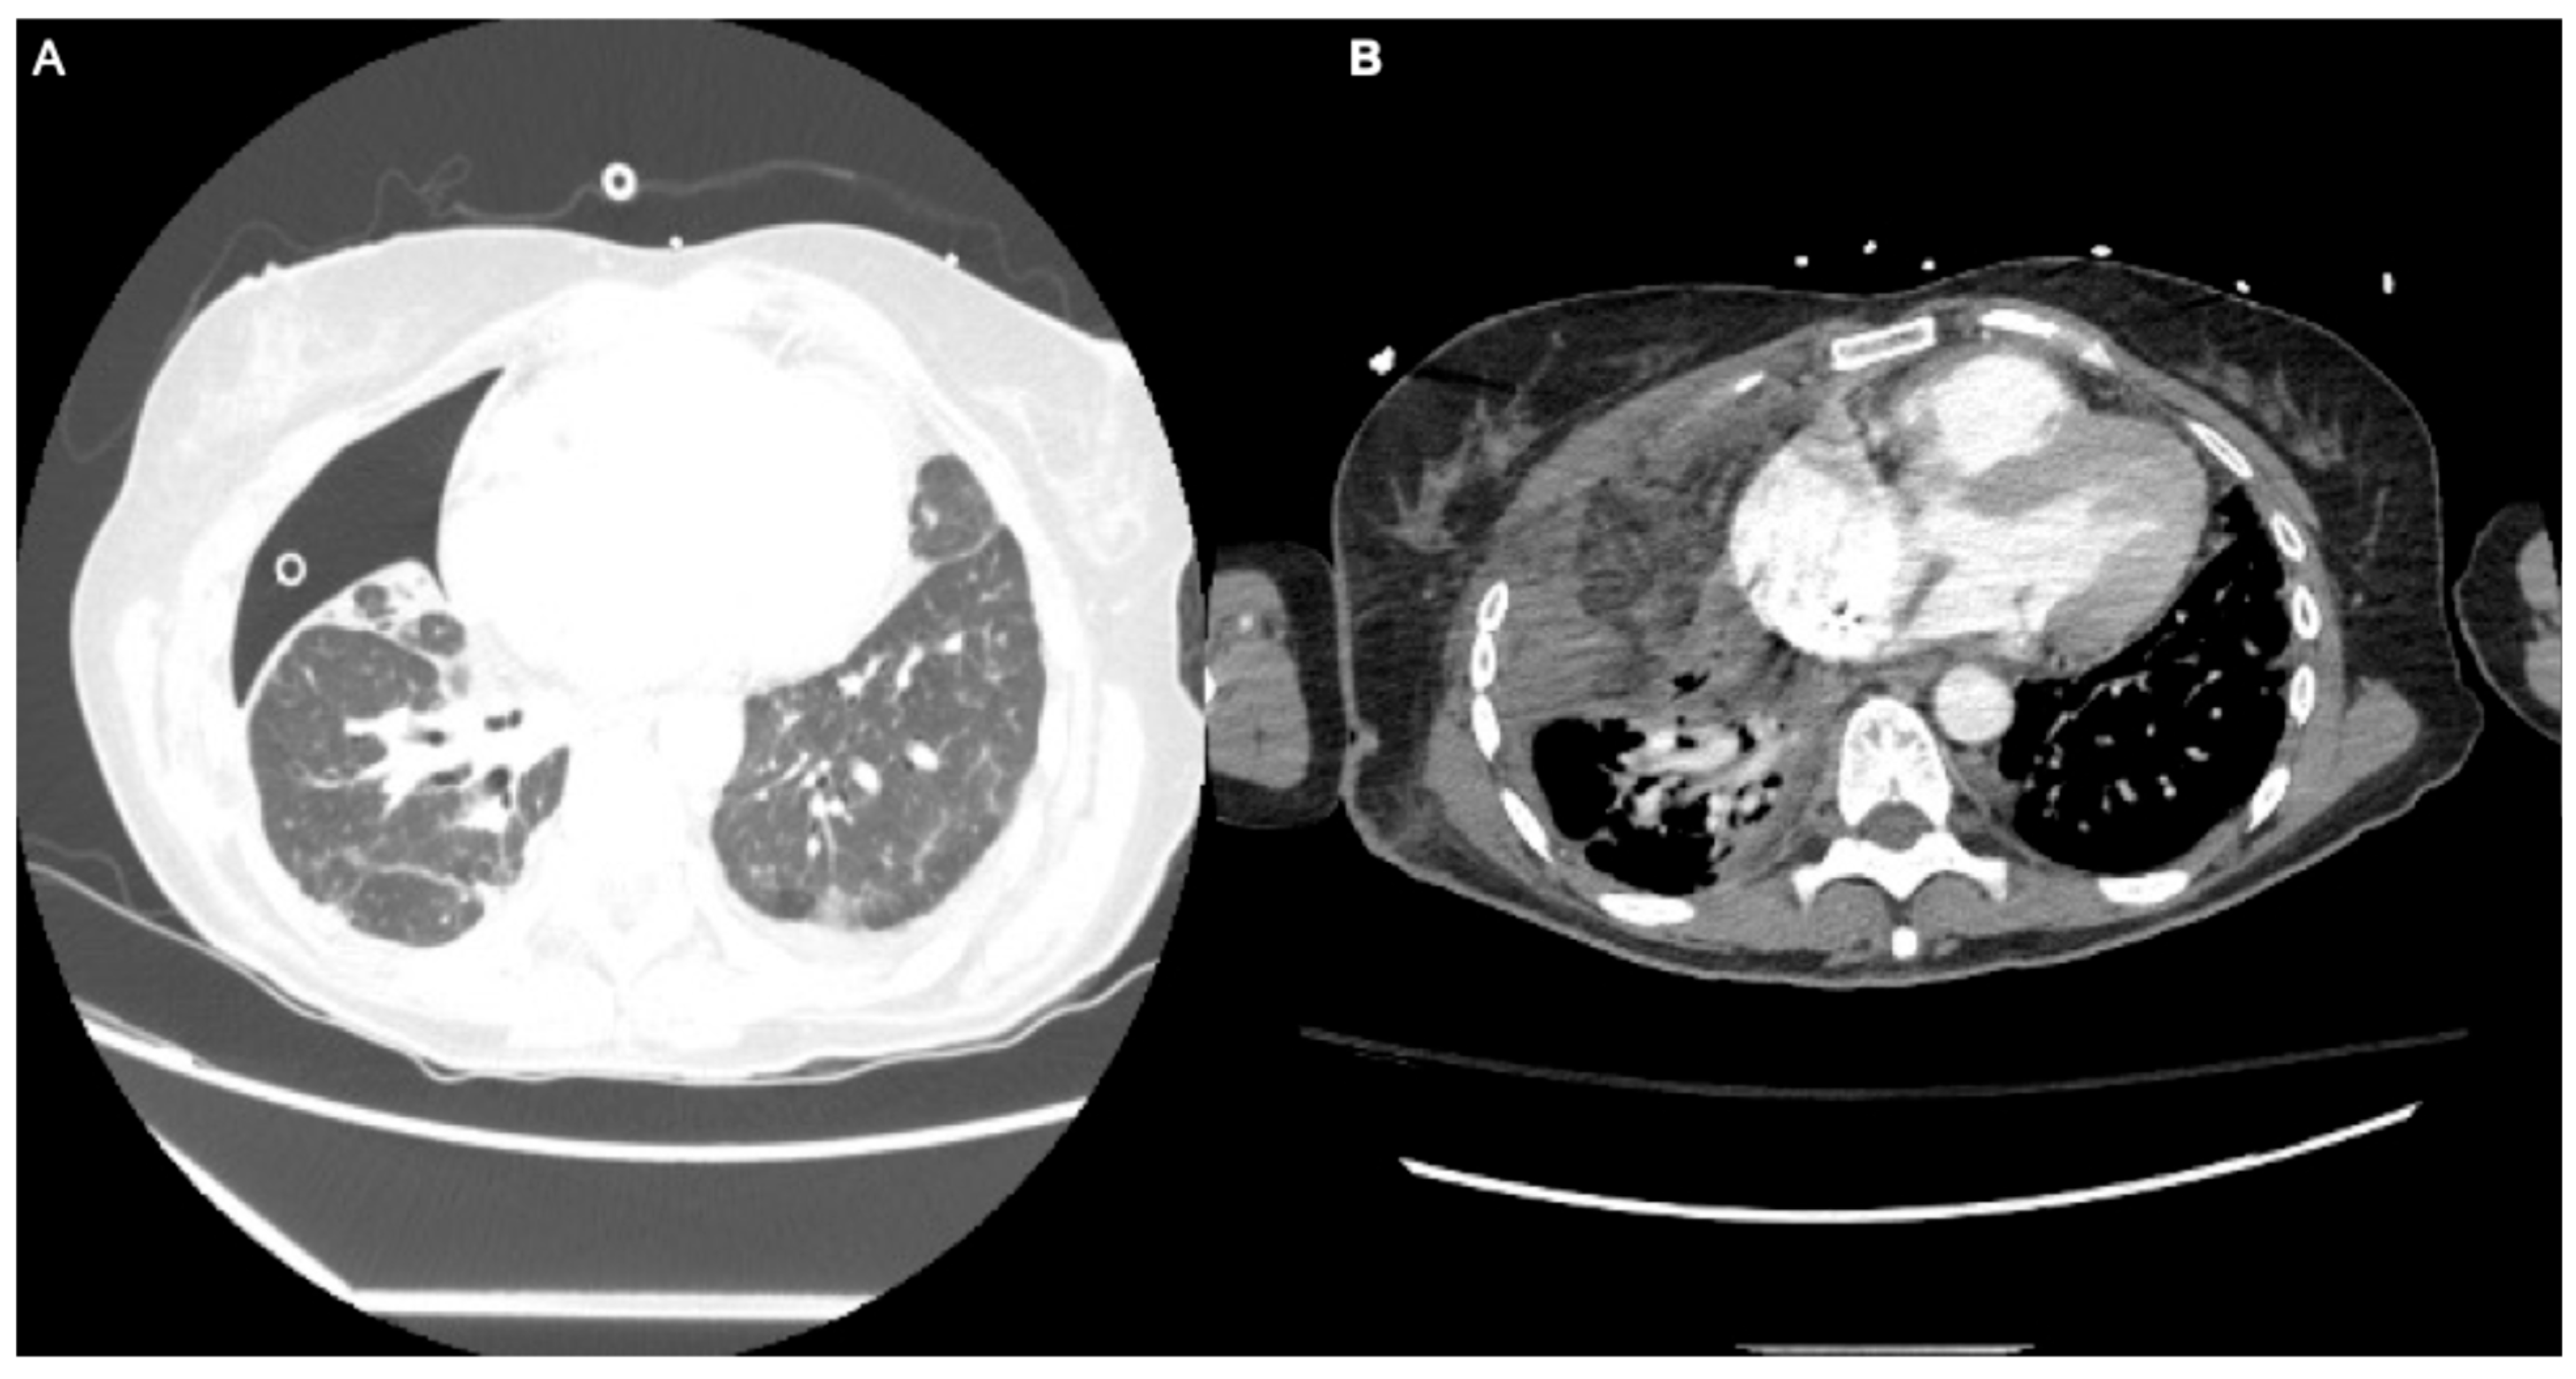

| A | 45 | M | Type 1 DM, alcohol abuse, smoking history, depression | Bronchopleural fistula, chest wall defect | Thoracotomy, empyema drainage, decortication, Eloesser flap | Robotic omental flap harvest, thoracotomy, flap transposition, chest wall closure | 67 | 500 | 3.0 | None | Excellent wound healing, no recurrence |

| B | 56 | F | Idiopathic pulmonary fibrosis, psoriasis, immunosuppression | Persistent air leak, trapped lung, empyema | Robotic wedge resection, VATS decortication, endobronchial valves | Robotic omental harvest, thoracotom, serratus flap, thoracoplasty | 98 | 500 | Respiratory failure, tracheostomy, PEG | Air leak resolved, discharged to LTACH, trach-dependent | |